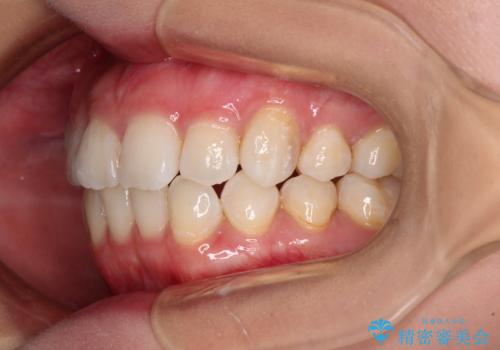

上顎の八重歯と下顎前歯の欠損 ワイヤー装置による抜歯矯正

- 上顎の八重歯を気にして来院された患者様です。

診察したところ、下顎前歯が2本欠損していたため、上下のバランスを取りながら八重歯を改善するため、上顎左右第一小臼歯2本を抜歯することとしました。

下顎前歯と本来抜歯矯正で抜歯する歯とは大きさが異なるため、仕上がりの咬み合わせは理想的なものとはなりませんでしたが、気になっていた八重歯はきれいに改善することができました。